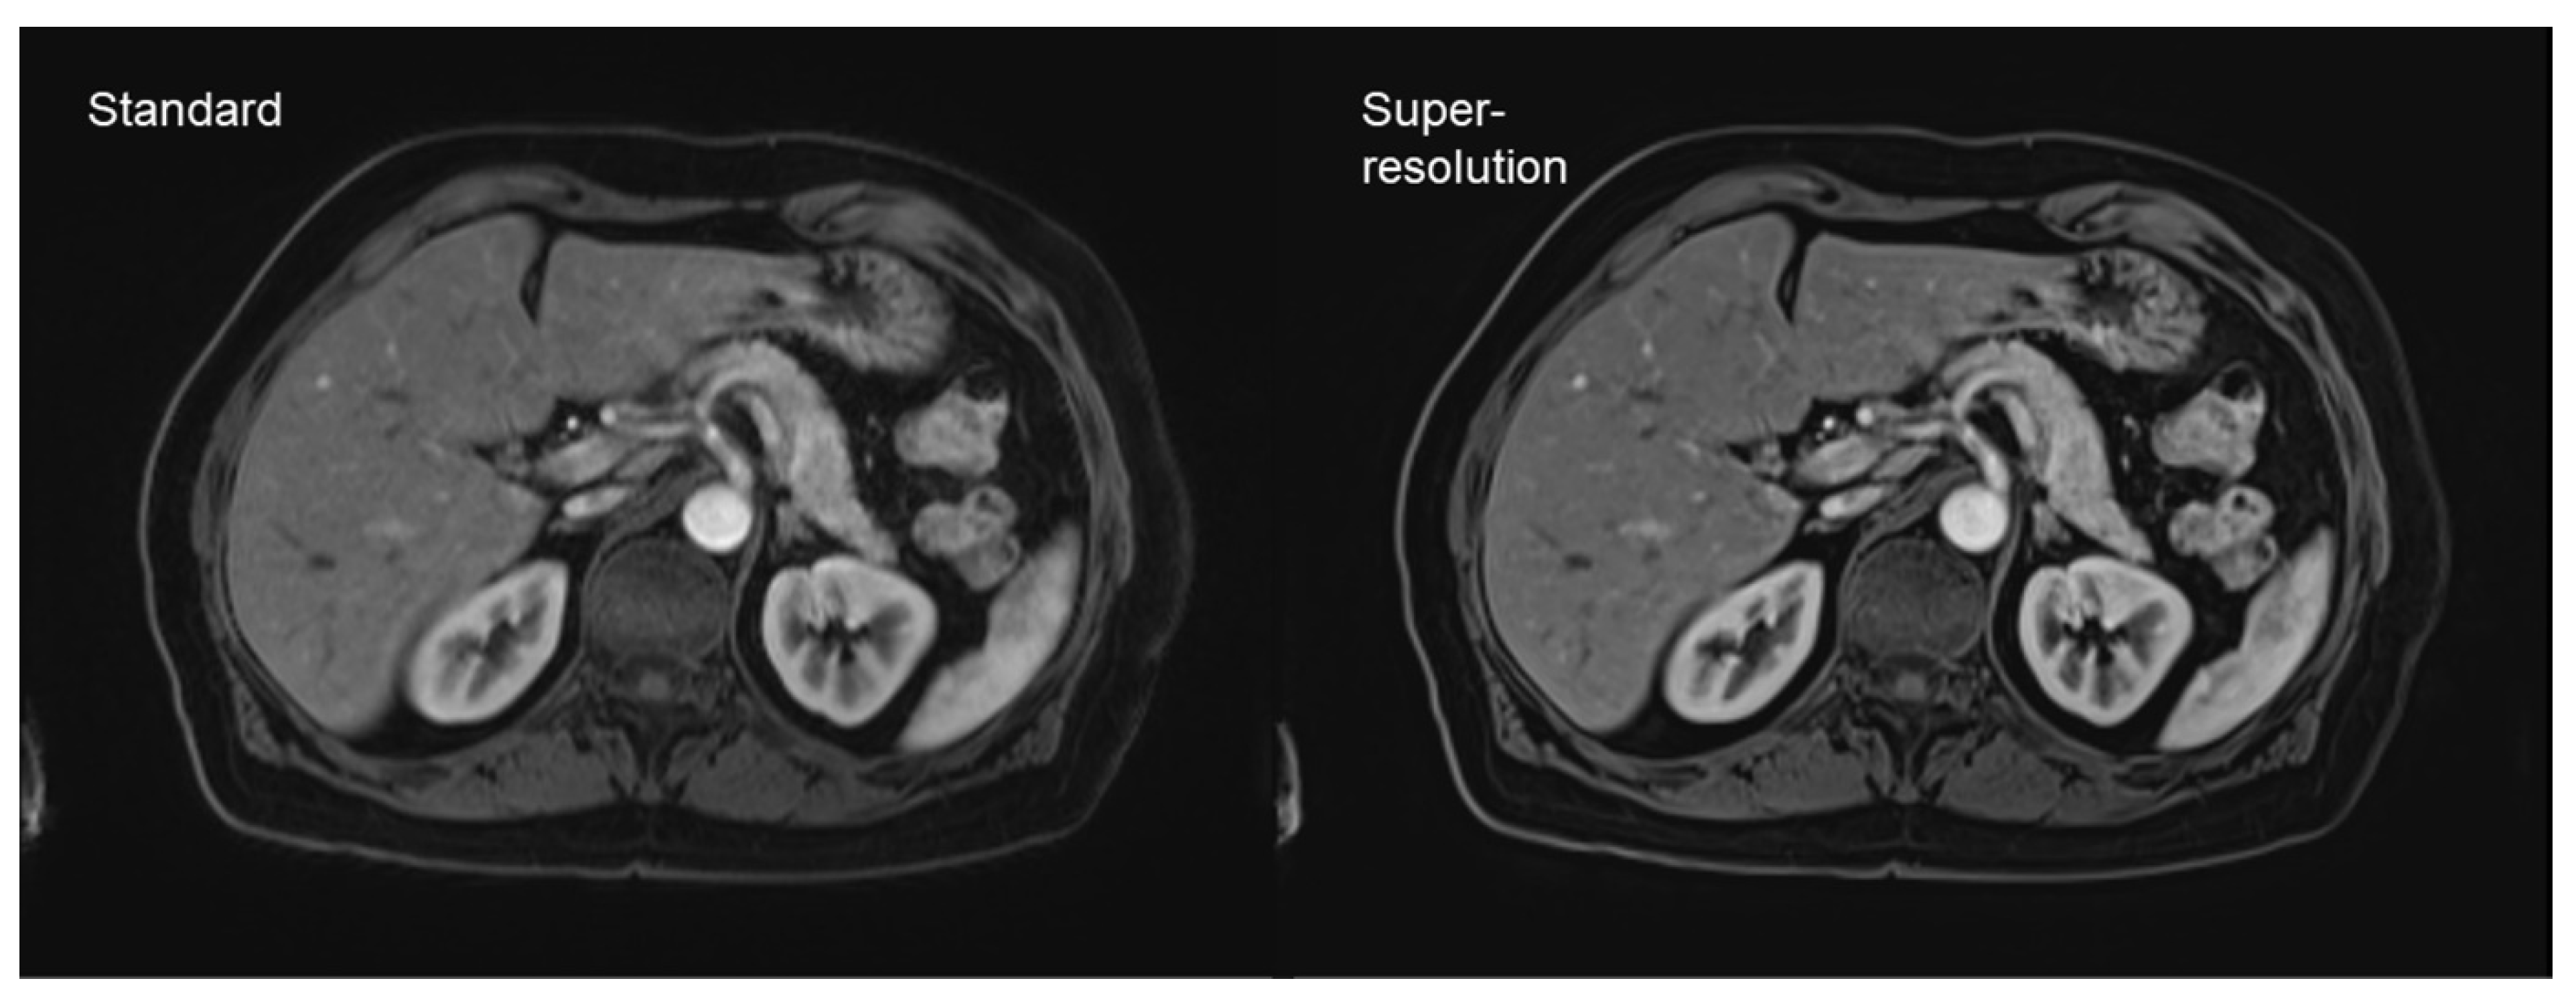

- Almansour, H.; Gassenmaier, S.; Nickel, D.; Kannengiesser, S.; Afat, S.; Weiss, J.; Hoffmann, R.; Othman, A.E. Deep Learning-Based Superresolution Re-construction for Upper Abdominal Magnetic Resonance Imaging: An Analysis of Image Quality, Diagnostic Confidence, and Lesion Conspicuity. Investig. Radiol. 2021, 56, 509–516. [Google Scholar] [CrossRef] [PubMed]

- Afat, S.; Wessling, D.; Afat, C.; Nickel, D.; Arberet, S.; Herrmann, J.; Othman, A.E.; Gassenmaier, S. Analysis of a Deep Learning-Based Superresolution Algorithm Tailored to Partial Fourier Gradient Echo Sequences of the Abdomen at 1.5 T: Reduction of Breath-Hold Time and Improvement of Image Quality. Investig. Radiol. 2021. [Google Scholar] [CrossRef] [PubMed]